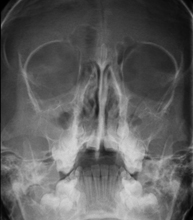

- Paranasal Sinuses X-ray

This technique uses X-ray rendered imaging for examining the paranasal sinuses. Indicated for: difficulty breathing through the nose, chronic cough, headache, mucus.